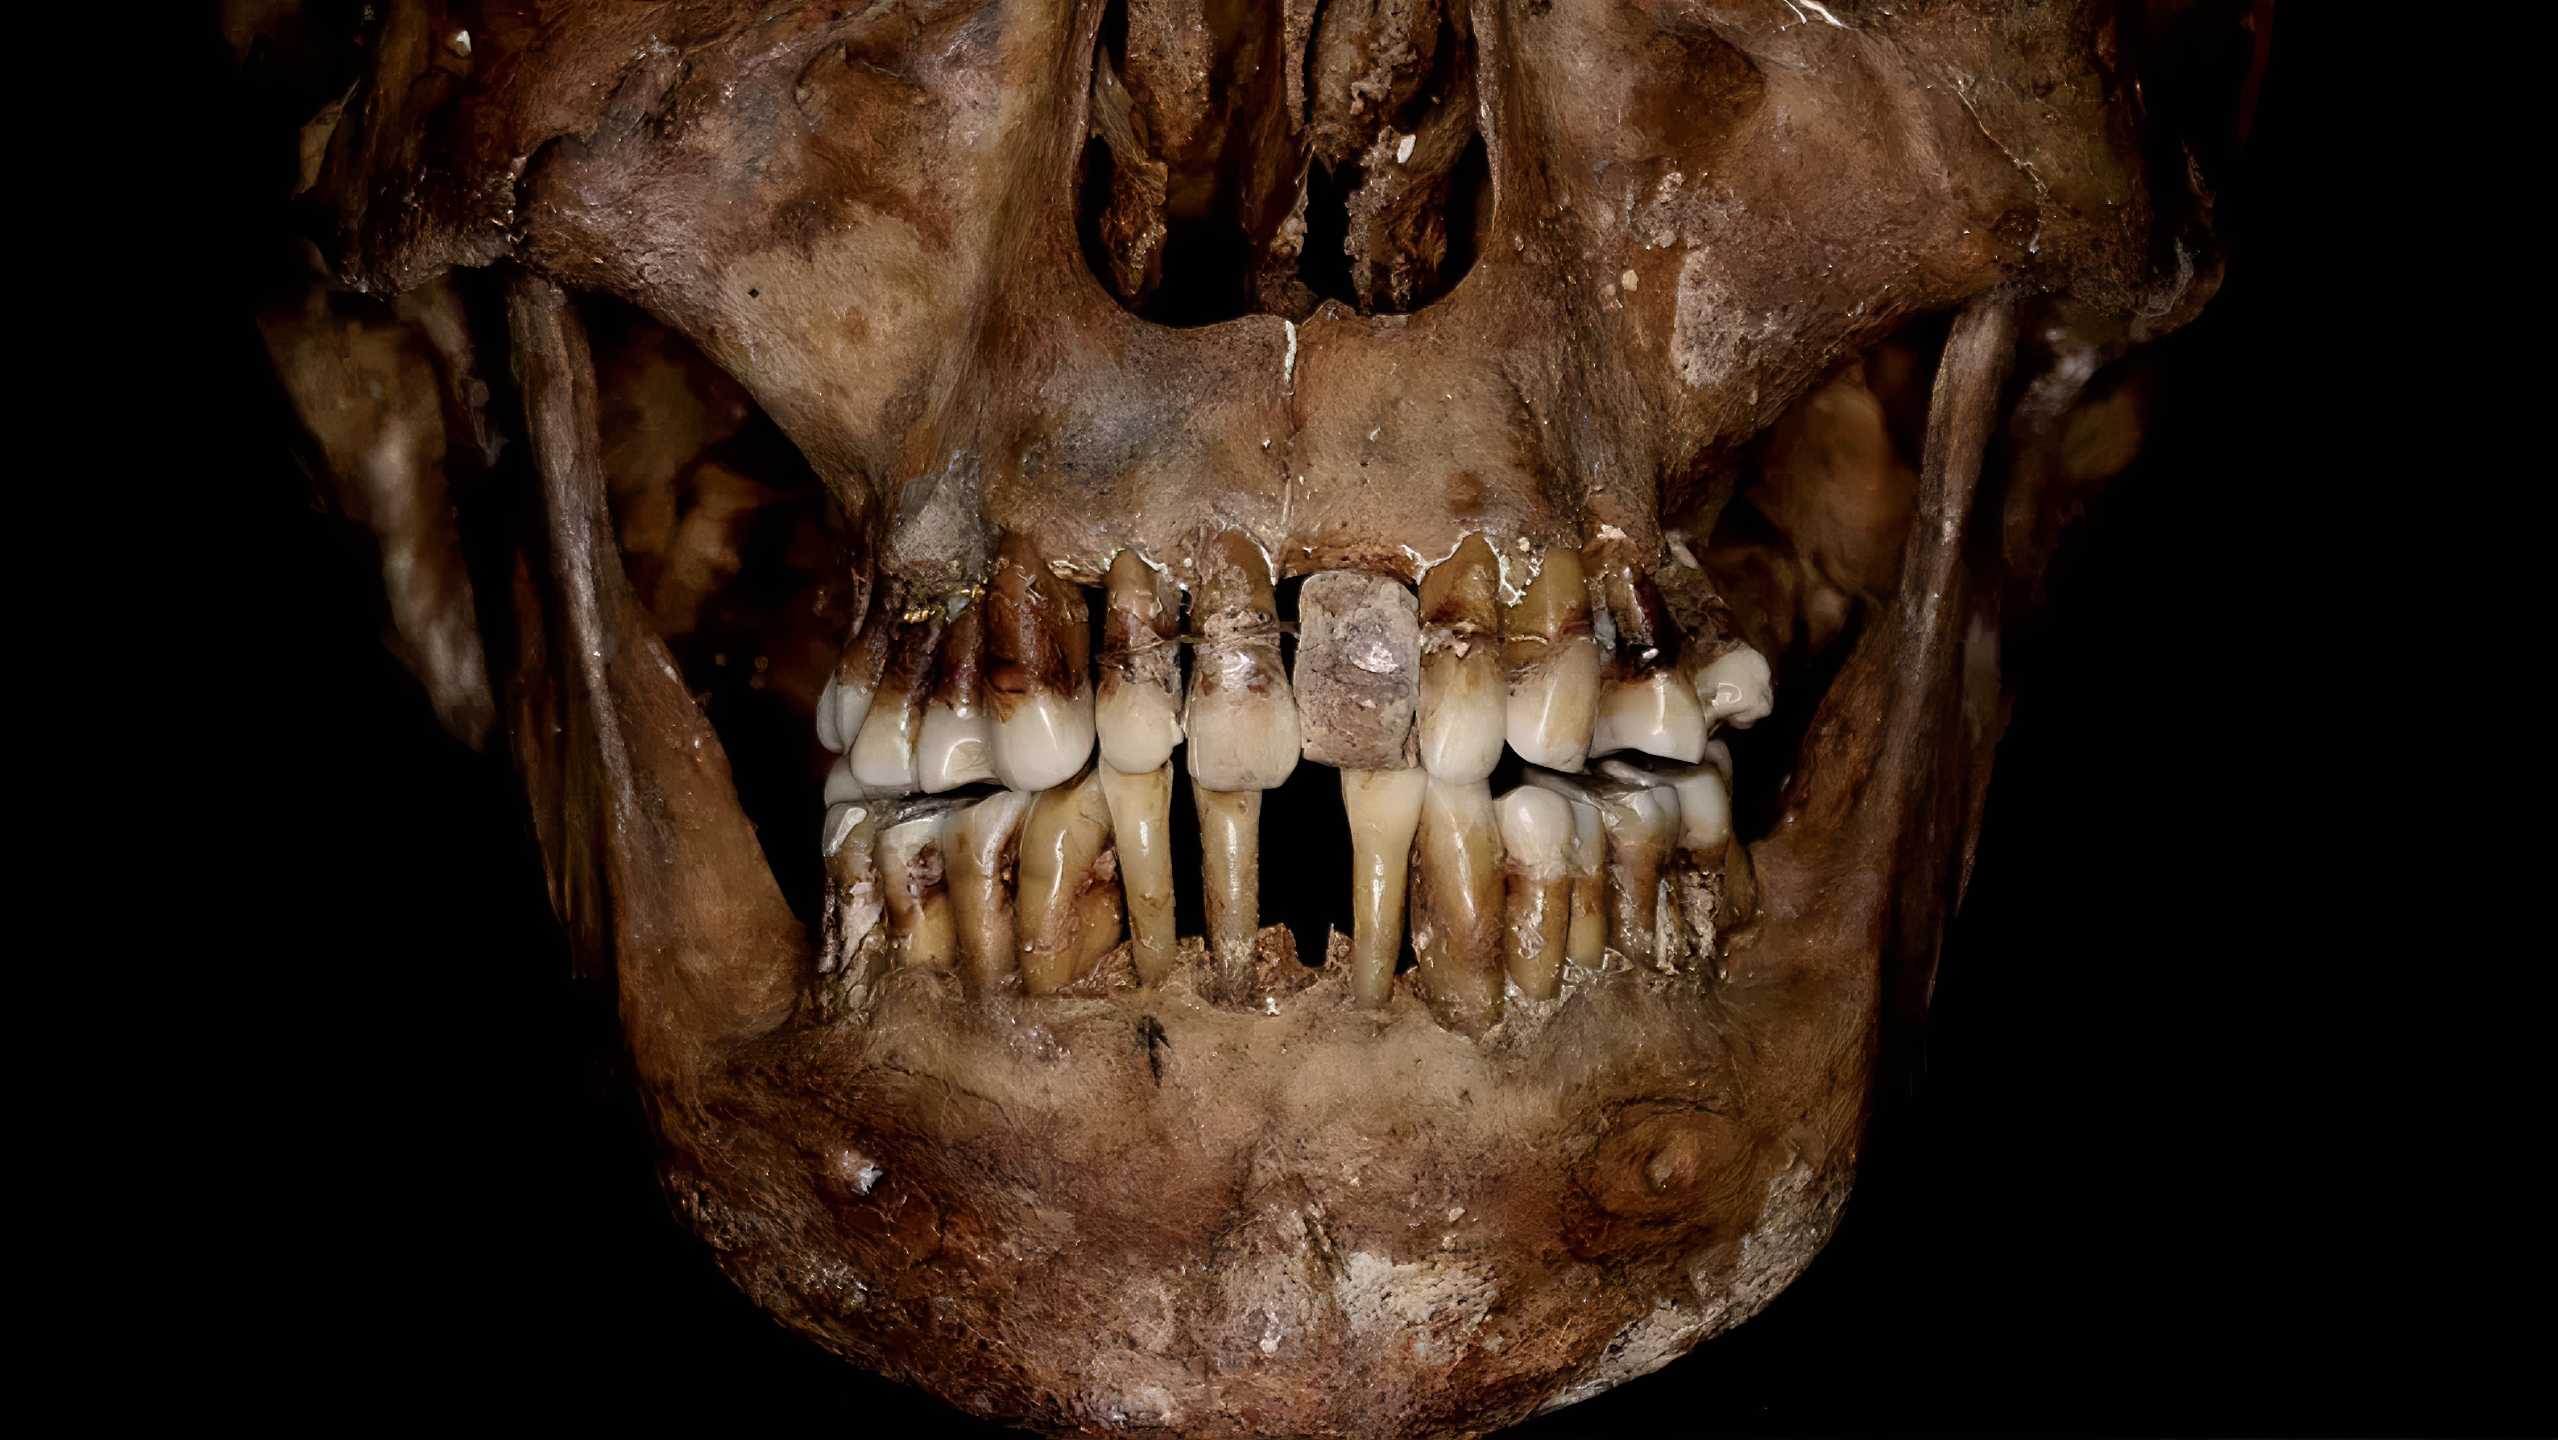

이 무렵 돈과 권력 있는 사람들 보면 대체로 납관lead coffin에 안치되는데, 이 분은 그에다가 방부처리embalmed까지 된 모양이라 이 덕분에 뼈와 이빨이 놀라울 정도로 보존 상태가 좋았다.

17세기 초 프랑스 귀족 사회 최상층을 구가하며 권력을 쥔 이 여인은 금 와이어로 이빨을 고정하고선 매혹적인 미소를 유지하려 했겠지만

프랑스 렌에 있는 국립 예방 고고학 연구소 National Institute for Preventive Archaeological Research (INRAP) 고고학도 로젠 콜레터Rozenn Colleter는 1988년 발굴 유골 중 이빨에서 가짜 이빨false tooth과 결찰ligatures(무언가를 묶는 데 사용되는 실이나 와이어의 의학 용어)이 있음을 발견했다. [false tooth가 무엇을 말하는지 모르겠다. 틀니인가?]

2023년 1월 24일 Journal of Archaeological Science: Reports에 공간된 연구성과에서 X선을 사용하여 3차원 이미지를 만드는 "콘 빔cone beam"으로 그의 두개골을 스캔한 결과 d'Alègre는 심각한 치주 질환periodontal disease을 앓았으며

이때문에 많은 치아가 느슨해졌고 그런 치아가 빠지지 않도록 미세한 금 와이어fine gold wires를 삽입했다는 사실이 밝혀냈다.

이 와이어는 잇몸 근처 치아 바닥을 감았다. 치아 중 일부는 와이어를 넣고자 뚫린 상태였고, 이미 이빨 일부가 빠져 그 부분은 코끼리 상아로 만든 가짜 치아도 넣었다. 임플란트? 시술 비슷하게 한 셈이다.